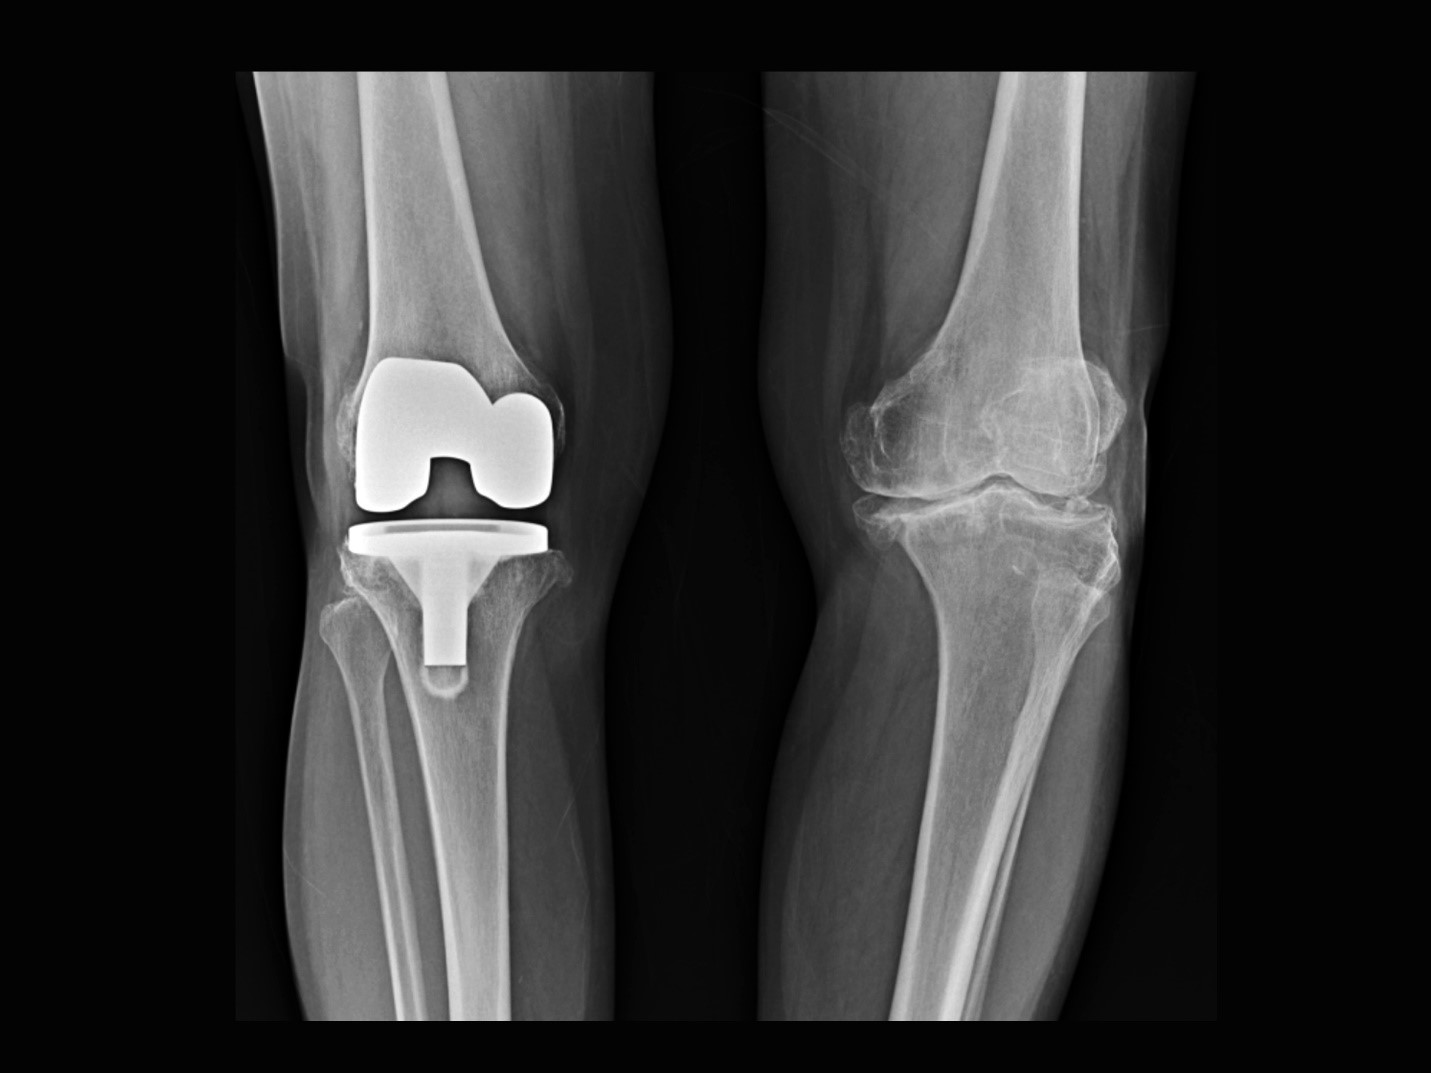

Our most successful knee pain treatment programs include: